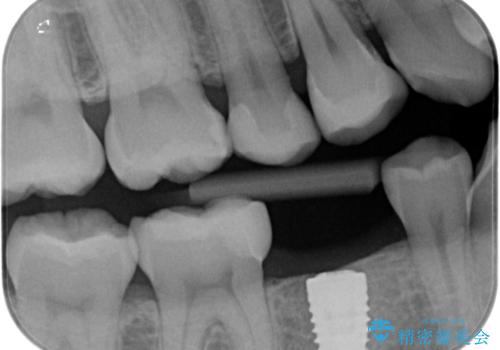

- 歯と歯の間に古い樹脂の治療がされていて虫歯の再発のリスクが高まるためにe-maxインレー(セラミック)治療を行いました。